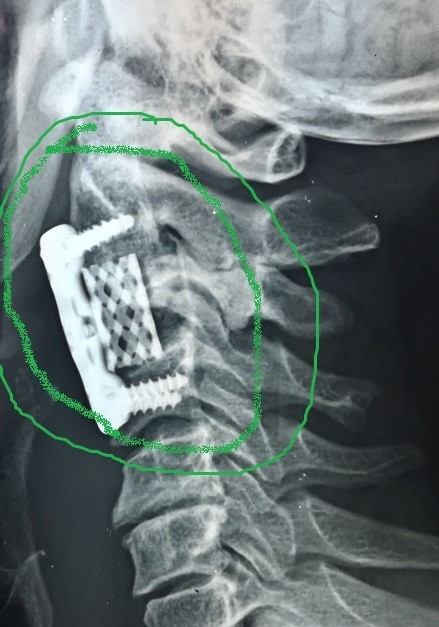

تثبيت امامي لكسر وتاكل بجسم الفقرة الثالثة العنقية

anterior fixation of a fracture and wear of the body of the third cervical vertebra

A successful anterior fixation surgery was performed to treat fracture and erosion in the vertebral body of cervical vertebrae. This specialized procedure aims to restore cervical spine stability and address vertebral damage resulting from injury or inflammation.

• Use of anterior approach for direct vertebral access

• Advanced internal fixation using plates and screws

• Replacement of damaged vertebral body with bone graft or implant